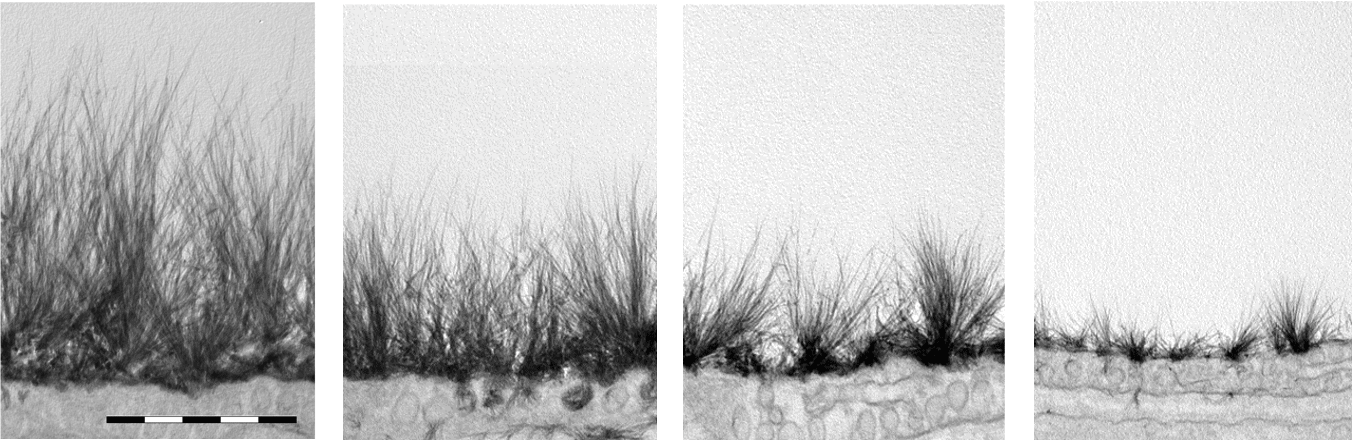

(LEFT) Cross-section of a capillary blood vessel in a rat heart muscle shows extensive dimension of the glycocalyx in a healthy blood vessel.

(RIGHT) High magnification showing the dimension of the glycocalyx is several fold the thickness of the endothelium.

Reference: Journal of Internal Medicine 2006; 259: 393–400

Healthy

Unhealthy